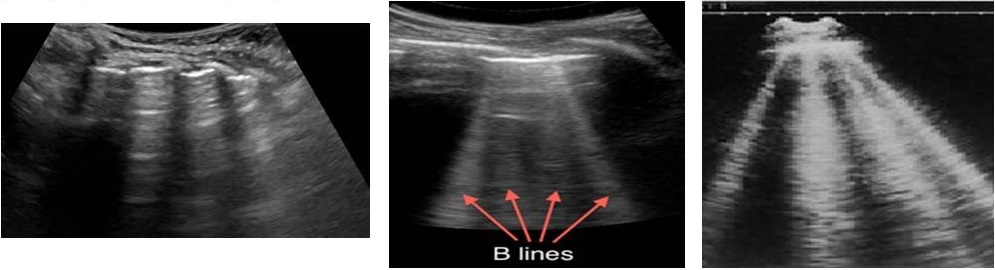

B-lines - correlates with interstitial oedema. They are comet tail artefacts, arising from pleural line, hyperechoic, laser beam like an artefact, long, without fading, erasing A-lines moving with lung sliding.

B lines present in any disease affecting the interstitium, interlobular septa surrounded by alveolar air. B lines are likely to represent fluid or fibrosis. Air in alveoli and water in the interlobular septa causes the sound to reverberate to and fro between the septa creating the line for each reverberation which combine to form B lines.

Two B lines – comet-tail artefact. Two or three B lines – lung rockets in interstitial syndrome. Three or four B lines indicate septal rockets due to edematous subpleural interlobular septa. B lines correlate with kerley B lines on chest Xray. Diffuse B line pattern represent cardiogenic or noncardiogenic pulmonary oedema or pneumonitis. Focal multiple B lines present posterolaterally in a normal lung seen in pneumonia, atelectasis, lung contusion and pulmonary infarcts. At least seven B lines are called ground glass rockets.